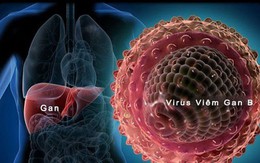

90% người mắc căn bệnh này không thể phát hiện ở giai đoạn sớm, đừng chủ quan với các dấu hiệu nguy hiểm này

17/09/2019 17:44

Theo thống kê của Bộ Y tế, cả nước đang có khoảng 10 triệu trường hợp nhiễm viêm gan B và 1 triệu người nhiễm virus viêm gan C, đáng lo ngại là 90% người bệnh không biết về tình trạng của mình. Nguyên nhân bởi đa số bệnh nhân đều bỏ qua các dấu hiệu viêm gan ở giai đoạn sớm sau đây.

“Kẻ giết người thầm lặng” này được coi nguy hiểm hơn cả HIV, cứ 10 người Việt lại có 1 người bị mắc bệnh

11/07/2019 21:04

Trên thế giới hiện nay Viêm gan B đang là căn bệnh phổ biến gây tử vong với tỷ lệ rất cao. Virus viêm gan B là tiền căn của các bệnh xơ gan, ung thư gan nếu không được phát hiện và điều trị kịp thời. Tại sao virus viêm gan B được nhận định còn nguy hiểm hơn cả virus HIV?